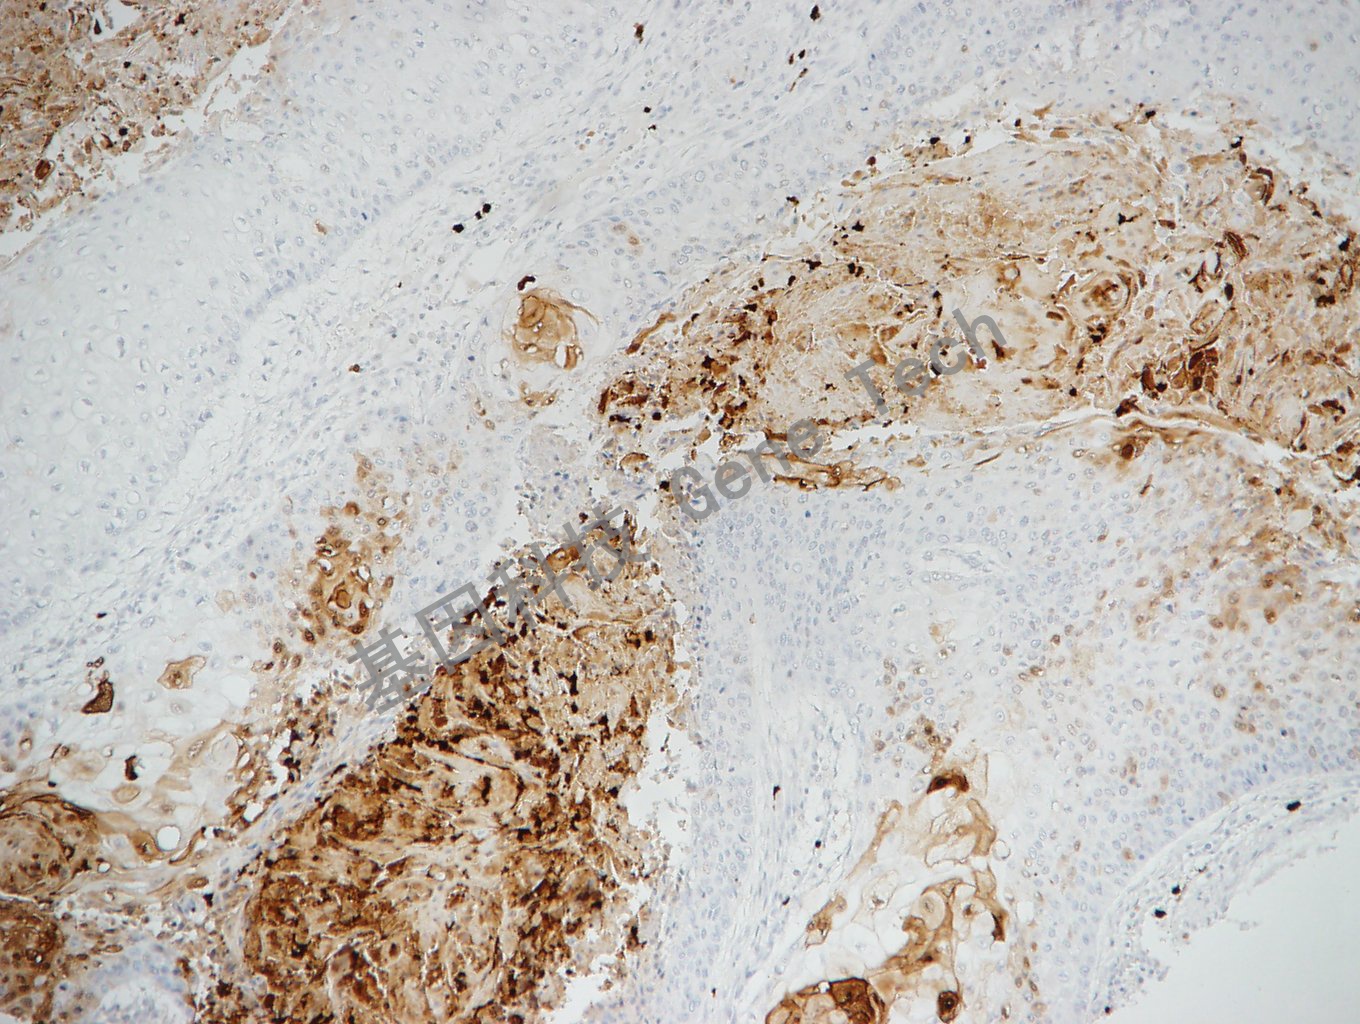

胰腺癌石蜡切片,用 S-100P(GT2286)染色,细胞浆/细胞核阳性,DAB显色。